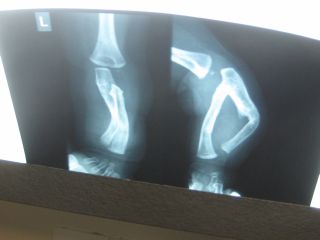

در

5 مورد، بيماران دچار ضايعات استخواني بودند که شامل استئوپوروز وكيفوز گردن به علت

نوروفيبروم (يك مورد)، نامنظمي لبه قدامي دندهها و نامنظمي برجستگي كلونوييد راست

و باريك شدن ترقوه راست (يك مورد)، كيفوز توراكولومبار و تخريب زينتركي (يك

مورد)، تخريب وسيع زينتركي و اسپينا بيفيدا (يك مورد)، كرانيوسينوستوز

(craniosynostosis)

و كيفواسكوليوز (يك مورد) بوده است.

در اين

مطالعه، استئوپوروز از ضايعات استخواني و كيفوز گردن به علت تومور گردن ، نامنظمي

لبه قدامي دندهها و كلنوييد راست و كيفواسيكوليوز لومبار و تخريب وسيع زينتركي،

اسپينا بيفيدا و كرانيوسينوستوز و ضايعات استخواني ستون فقرات ديده شد.

. ضايعات

استخواني در نوروفيبروماتوز طيف وسيعي را از پسودوآرتروز مادرزادي7،

اختلالات ديستروفيك ستون مهرهاي به علت نوروفيبروماتوز كه نياز به جراحي قوس قدامي

و خلفي دارند8 تا افزايش رشد يك اندام به طور مادرزادي را شامل ميشود9و4.